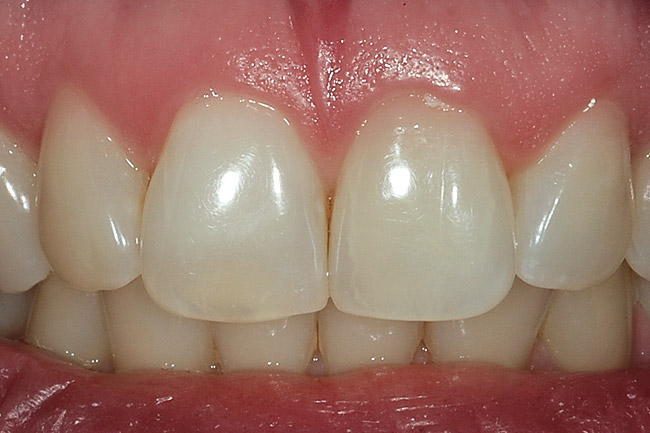

Figure 11  The 10% carbamide peroxide bleaching material was applied externally with the single-tooth bleaching tray nightly until the shade of the endodontically treated tooth returned to match the adjacent teeth. Should the tooth re-darken again, the process can be repeated without danger to the tooth. Figure 10 and Figure 11 courtesy of Meigan Johnson.

Figure 11